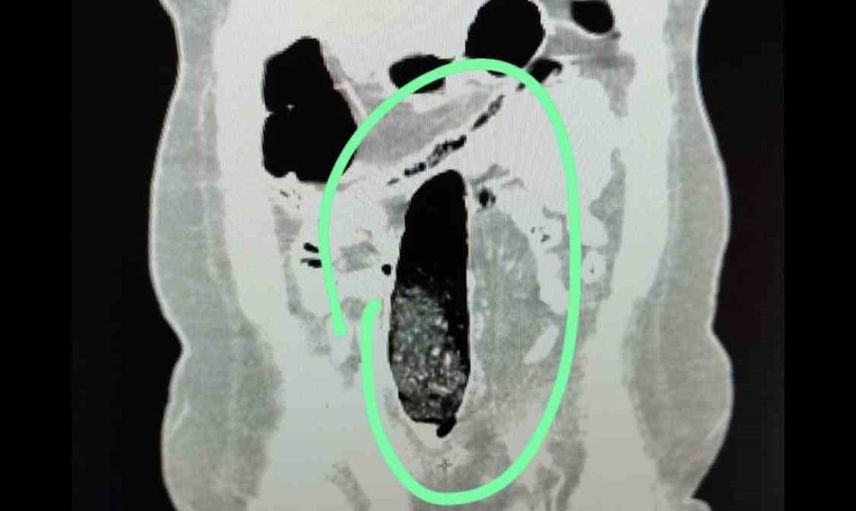

Durdurulan şehirler arası yolcu otobüsünde bulunan 2 İran uyruklu şahıs üzerinde yapılan kontrollerde şüpheli durum tespit edildi. Yapılan iç beden muayeneleri sonucunda şahısların vücutlarının doğal boşluklarında ve bağırsaklarında uyuşturucu madde bulunduğu belirlendi.

Tıbbi müdahale sonucu, F.V. isimli kadın şahıstan 3 parça halinde toplam 397,78 gram metamfetamin, S.İ. isimli erkek şahıstan ise 24 adet sentetik hap ile 3 parça halinde toplam 167,68 gram metamfetamin ele geçirildi.